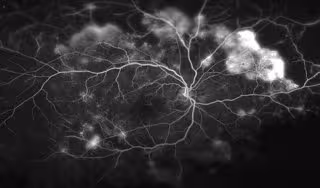

Foto: WILMER PHOTOGRAPHY

La retinopatía diabética es una dolencia ocular que puede aparecer en las personas que sufren una diabetes, principalmente aquellas que no tienen un buen control de su dolencia, que puede conducir a una pérdida severa de visión o incluso a la ceguera. De hecho, esta dolencia es la principal causa de ceguera en la población de edad laboral en los países industrializados y supone una importante fuente de consumo de recursos sanitarios.

La retinopatía diabética es la causa más común de pérdida de visión en los adultos en edad de trabajar en Estados Unidos, y se produce cuando los vasos sanguíneos normales en el ojo son reemplazados con el tiempo, con vasos sanguíneos anormales permeables y frágiles que dejan escapar fluido o sangran en el ojo, dañando la retina sensible a la luz y provocando ceguera. Entre el 40 y el 45 por ciento de los estadounidenses con diabetes sufre retinopatía diabética, según el Instituto Nacional del Ojo.